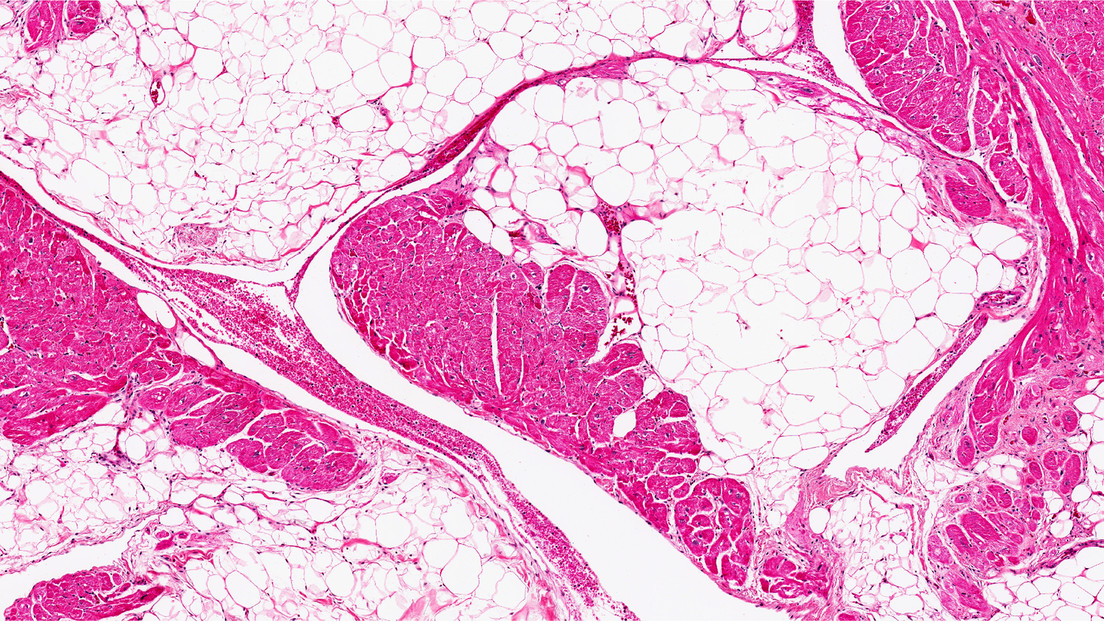

Lo más importante es que el primer grupo perdió grasa visceral, la más peligrosa porque se acumula en la cavidad abdominal, alrededor de los órganos principales. Estos ratones también mostraron un aumento en los niveles de insulina y glucosa en sangre.

Inesperadamente, la pérdida de grasa no se asoció con una menor ingesta de alimentos o un metabolismo más rápido. En cambio, los investigadores descubrieron que la TSLP estimulaba el sistema inmunológico para liberar lípidos a través de las glándulas sebáceas, productoras de sudor aceitoso en la piel.